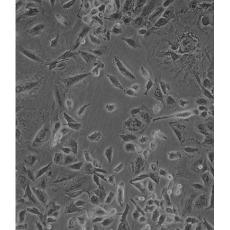

NCI-H1975

產品名稱 NCI-H1975

中文名稱 人肺腺癌細胞

組織來源 肺腺癌;女性

細胞種屬 Homo sapiens, human

生長特性 adherent

形態特征 epithelial

細胞描述 該細胞是1988年7月從一名女性(無抽煙史)非小細胞肺腺癌組織中分離得到的。